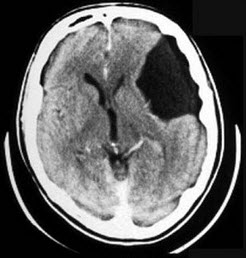

根据图示,应诊断为何种神经系统先天性疾病( )

A:颅底凹陷症

B:Litter病

C:无脑畸形

D:先天性脑积水

E:蛛网膜囊肿